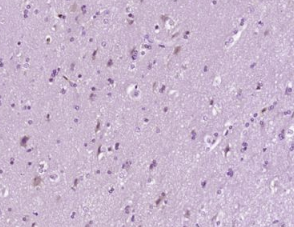

多聚甲醛固定,石蜡包埋(人脑胶质瘤);用柠檬酸钠缓冲液(pH6.0)煮沸15min后获得抗原;用3%过氧化氢阻断内源性过氧化物酶20分钟;阻断缓冲液(正常山羊血清)在37℃下30min;用Bax单克隆抗体进行抗体孵育。未结合的NAL抗体在4°C的1:400下过夜,然后根据SP试剂盒(小鼠)说明和DAB染色进行操作。